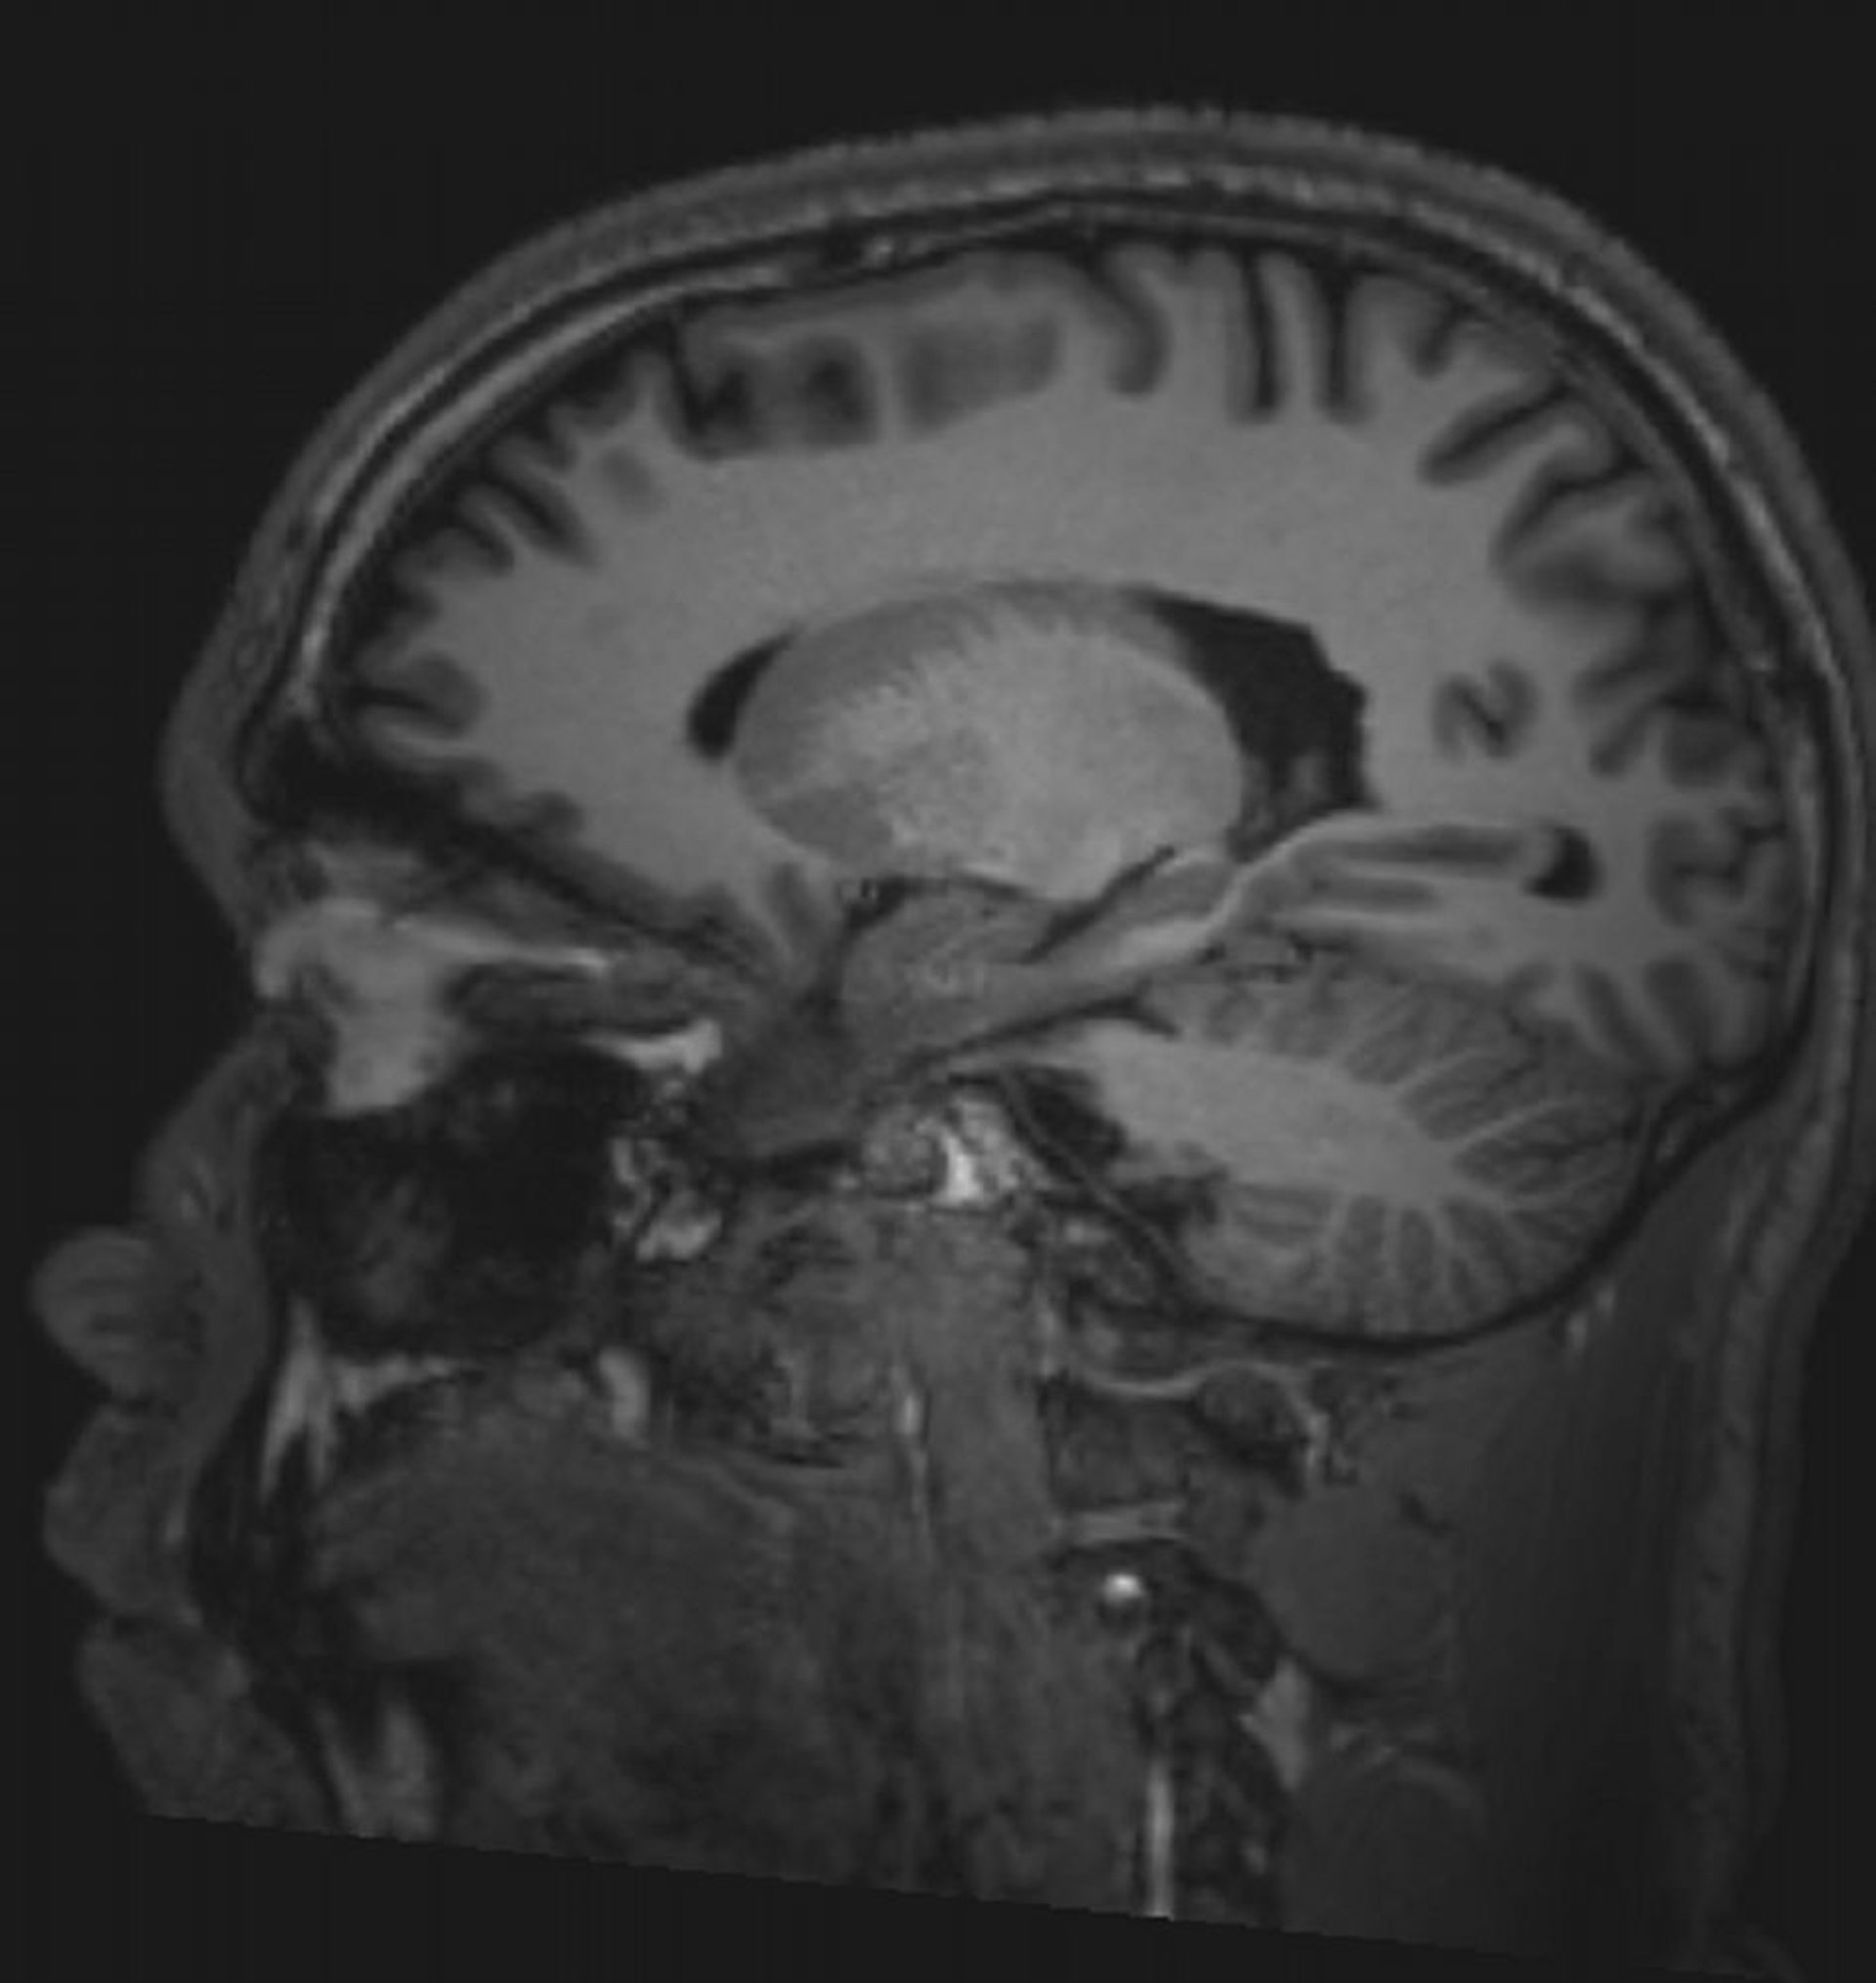

RM cerebral normal (sagital)–diapositiva 5

© 2017 Elliot K. Fishman, MD.